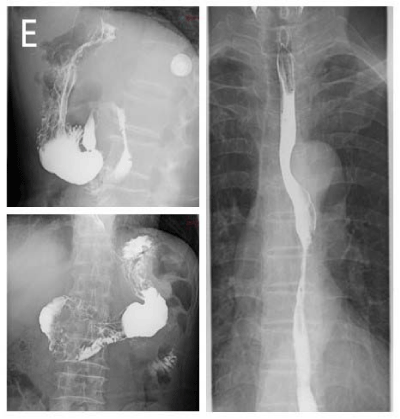

A 67-year-old man complained of intermittent upper abdominal distension. Gastroscopy showed that high-grade intraepithelial neoplasia of esophageal squamous growth 29cm from the incisors (Figure A), He underwent the ESD for the esophagus lesion (Figure B), pathologic proved that squamous cell carcinoma invaded the submucosa with a depth of more than 750 um. Computed tomogram (CT) of Chest and abdomen showed thickening of the middle esophageal wall, considering esophageal cancer, lesions between the stomach at the lower esophagus and cardia, and the possibility of stromal tumors or leiomyomas (Figure C, D). Barium meal of upper digestive tract asserted equally the rigid and filling defect of middle thoracic esophageal tube wall was observed, and no obvious niche and filling defect was found in gastric wall (Figure E). Because of the attack of cerebral infarction, the patient rejected the surgery and refuse to the chemotherapy in the followup planning. He underwent radiation therapy only for the primary esophagus. A 3D-CRT plan was designed, the planning target volume (PTV) was 60Gy in 30 fractions. After the recovery of the radiotherapy, and patients received the resection of partial gastrectomy plus small curvature lymphadenectomy. The operation showing that the tumors were located on the lesser curved side of the stomach, with a diameter of about 3cm, and there was a swollen lymph node with a diameter of about 2.5cm. Postoperative pathology showed moderately differentiated squamous cell carcinoma, local cancer tissue adjacent to the incision margin, considered as esophageal cancer proliferation, the left gastric lymph node also showed moderately differentiated squamous cell carcinoma. A follow-up study was performed 2 months after the surgery, no recurrence and metastasis was found.

Figure E: From 26 to 34 cm from the incisor, the mucosa was slightly rough, the surface was reddish and the edge was irregular, irregular light or nonstaining areas were observed after iodine staining. Normal saline, sodium hyaluronate and kidney were injected under the mucosa. ESD was performed